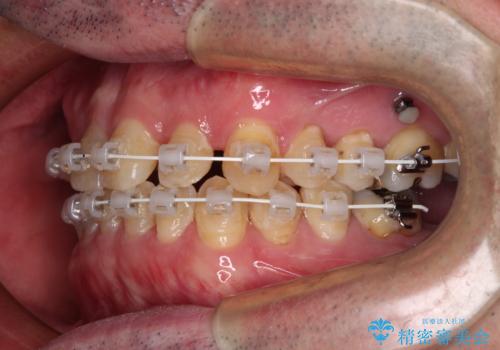

矯正治療は、ワイヤー装置とマウスピース矯正との選択肢がありましたが、マウスピース矯正は自己管理が煩わしいことを気にされて、目立たないワイヤー装置にて行うこととしました。

インプラント埋入による仮歯の装着や、前歯の反対咬合の改善は比較的スムーズに達成されましたが、舌突出癖などの影響による、歯列全体のスペースを閉じることが難航し、期間がかかってしまいました。